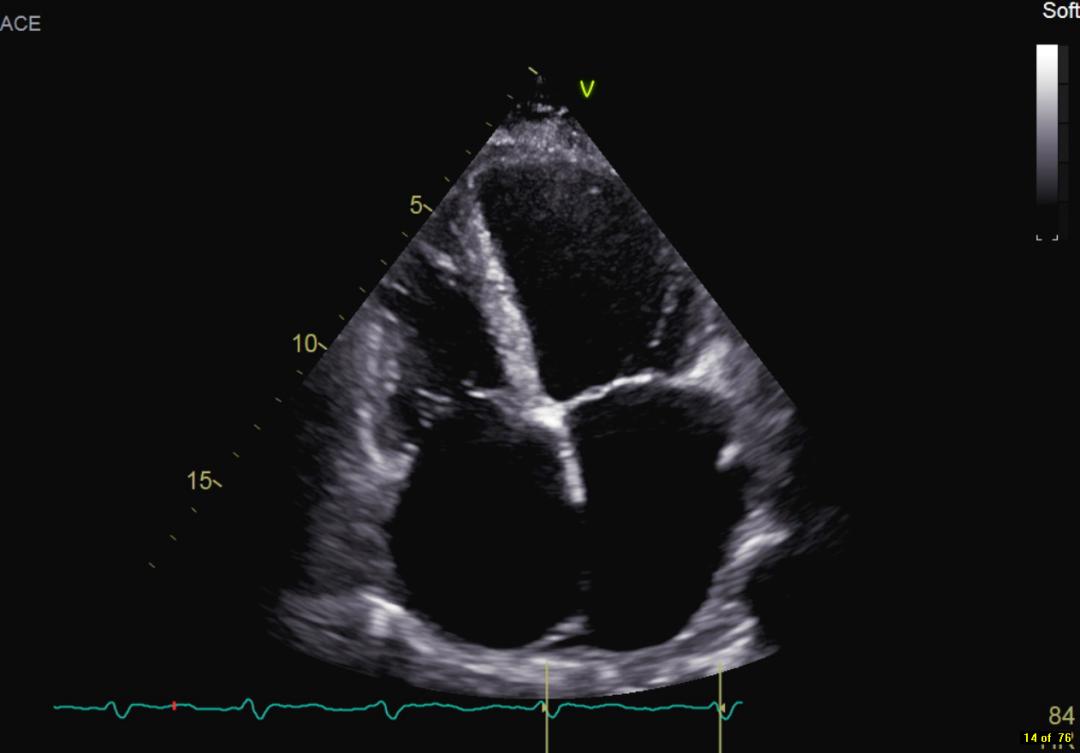

患者自述于其他医院诊断为扩张型心肌病,为进一步确认病情,吉心影像科医生为于女士进行了细致的检查。患者心电图结果显示心律失常,心房颤动,心脏彩超结果显示全心增大,二尖瓣回声增强增厚,瓣叶开放略受限,瓣叶关闭对合不良,三尖瓣开放幅度正常,关闭对合不良,左室及右室运动幅度减低。心脏超声结果显示二尖瓣关闭不全、三尖瓣关闭不全、左室收缩及舒张功能减低,右室收缩及舒张功能减低。

术前彩超影像